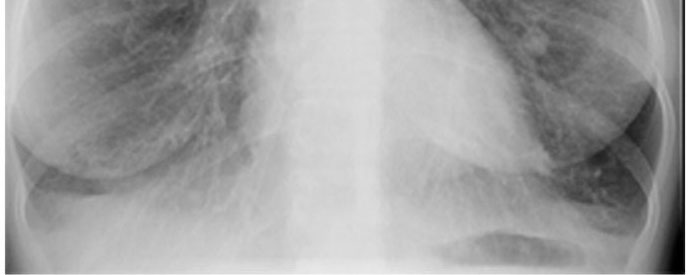

- La Radiographie standard ( cliche de

face et de profile ).